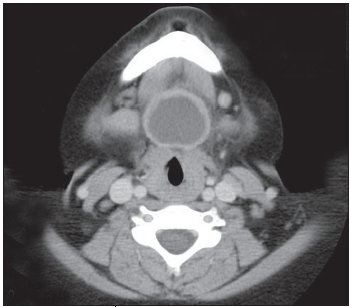

The complete blood cell count was normal, and blood culture was sterile. CT scans of the neck with contrast showed a well-defined, round cystic mass, with a homogeneous low- attenuation center and a ringlike enhancement in the midline immediately anterior and inferior to the hyoid bone (Figure). There was no evidence of significant fat around the nodes adjacent to the mass, and the airway was patent. The parotid and thyroid glands were within normal limits. These findings were thought to be consistent with an infected thyroglossal duct cyst (TGDC).